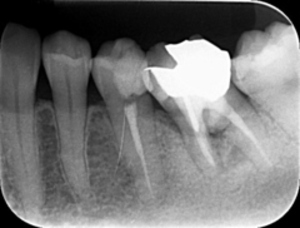

歯周病が進行し、グラグラして物が嚙めず、抜歯してインプラントにしていくことに。

インプラントはストローマンを使用、上部構造はジルコニアセラミックス